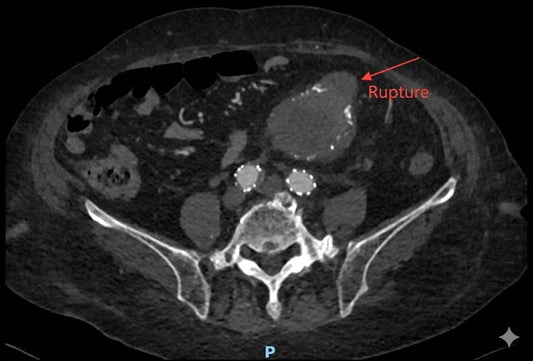

Managing Medically Refractory Acute Stroke: Cli...

This case highlights a 68-year-old female patient whose neurological status rapidly deteriorated to complete hemiplegia despite medical therapy. The Expert Team at Beijing Fuwai Hospital successfully restored TICI Grade 3...